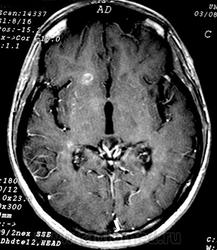

ГМ. Рассеянный склероз 3. +

Рассеянный склероз